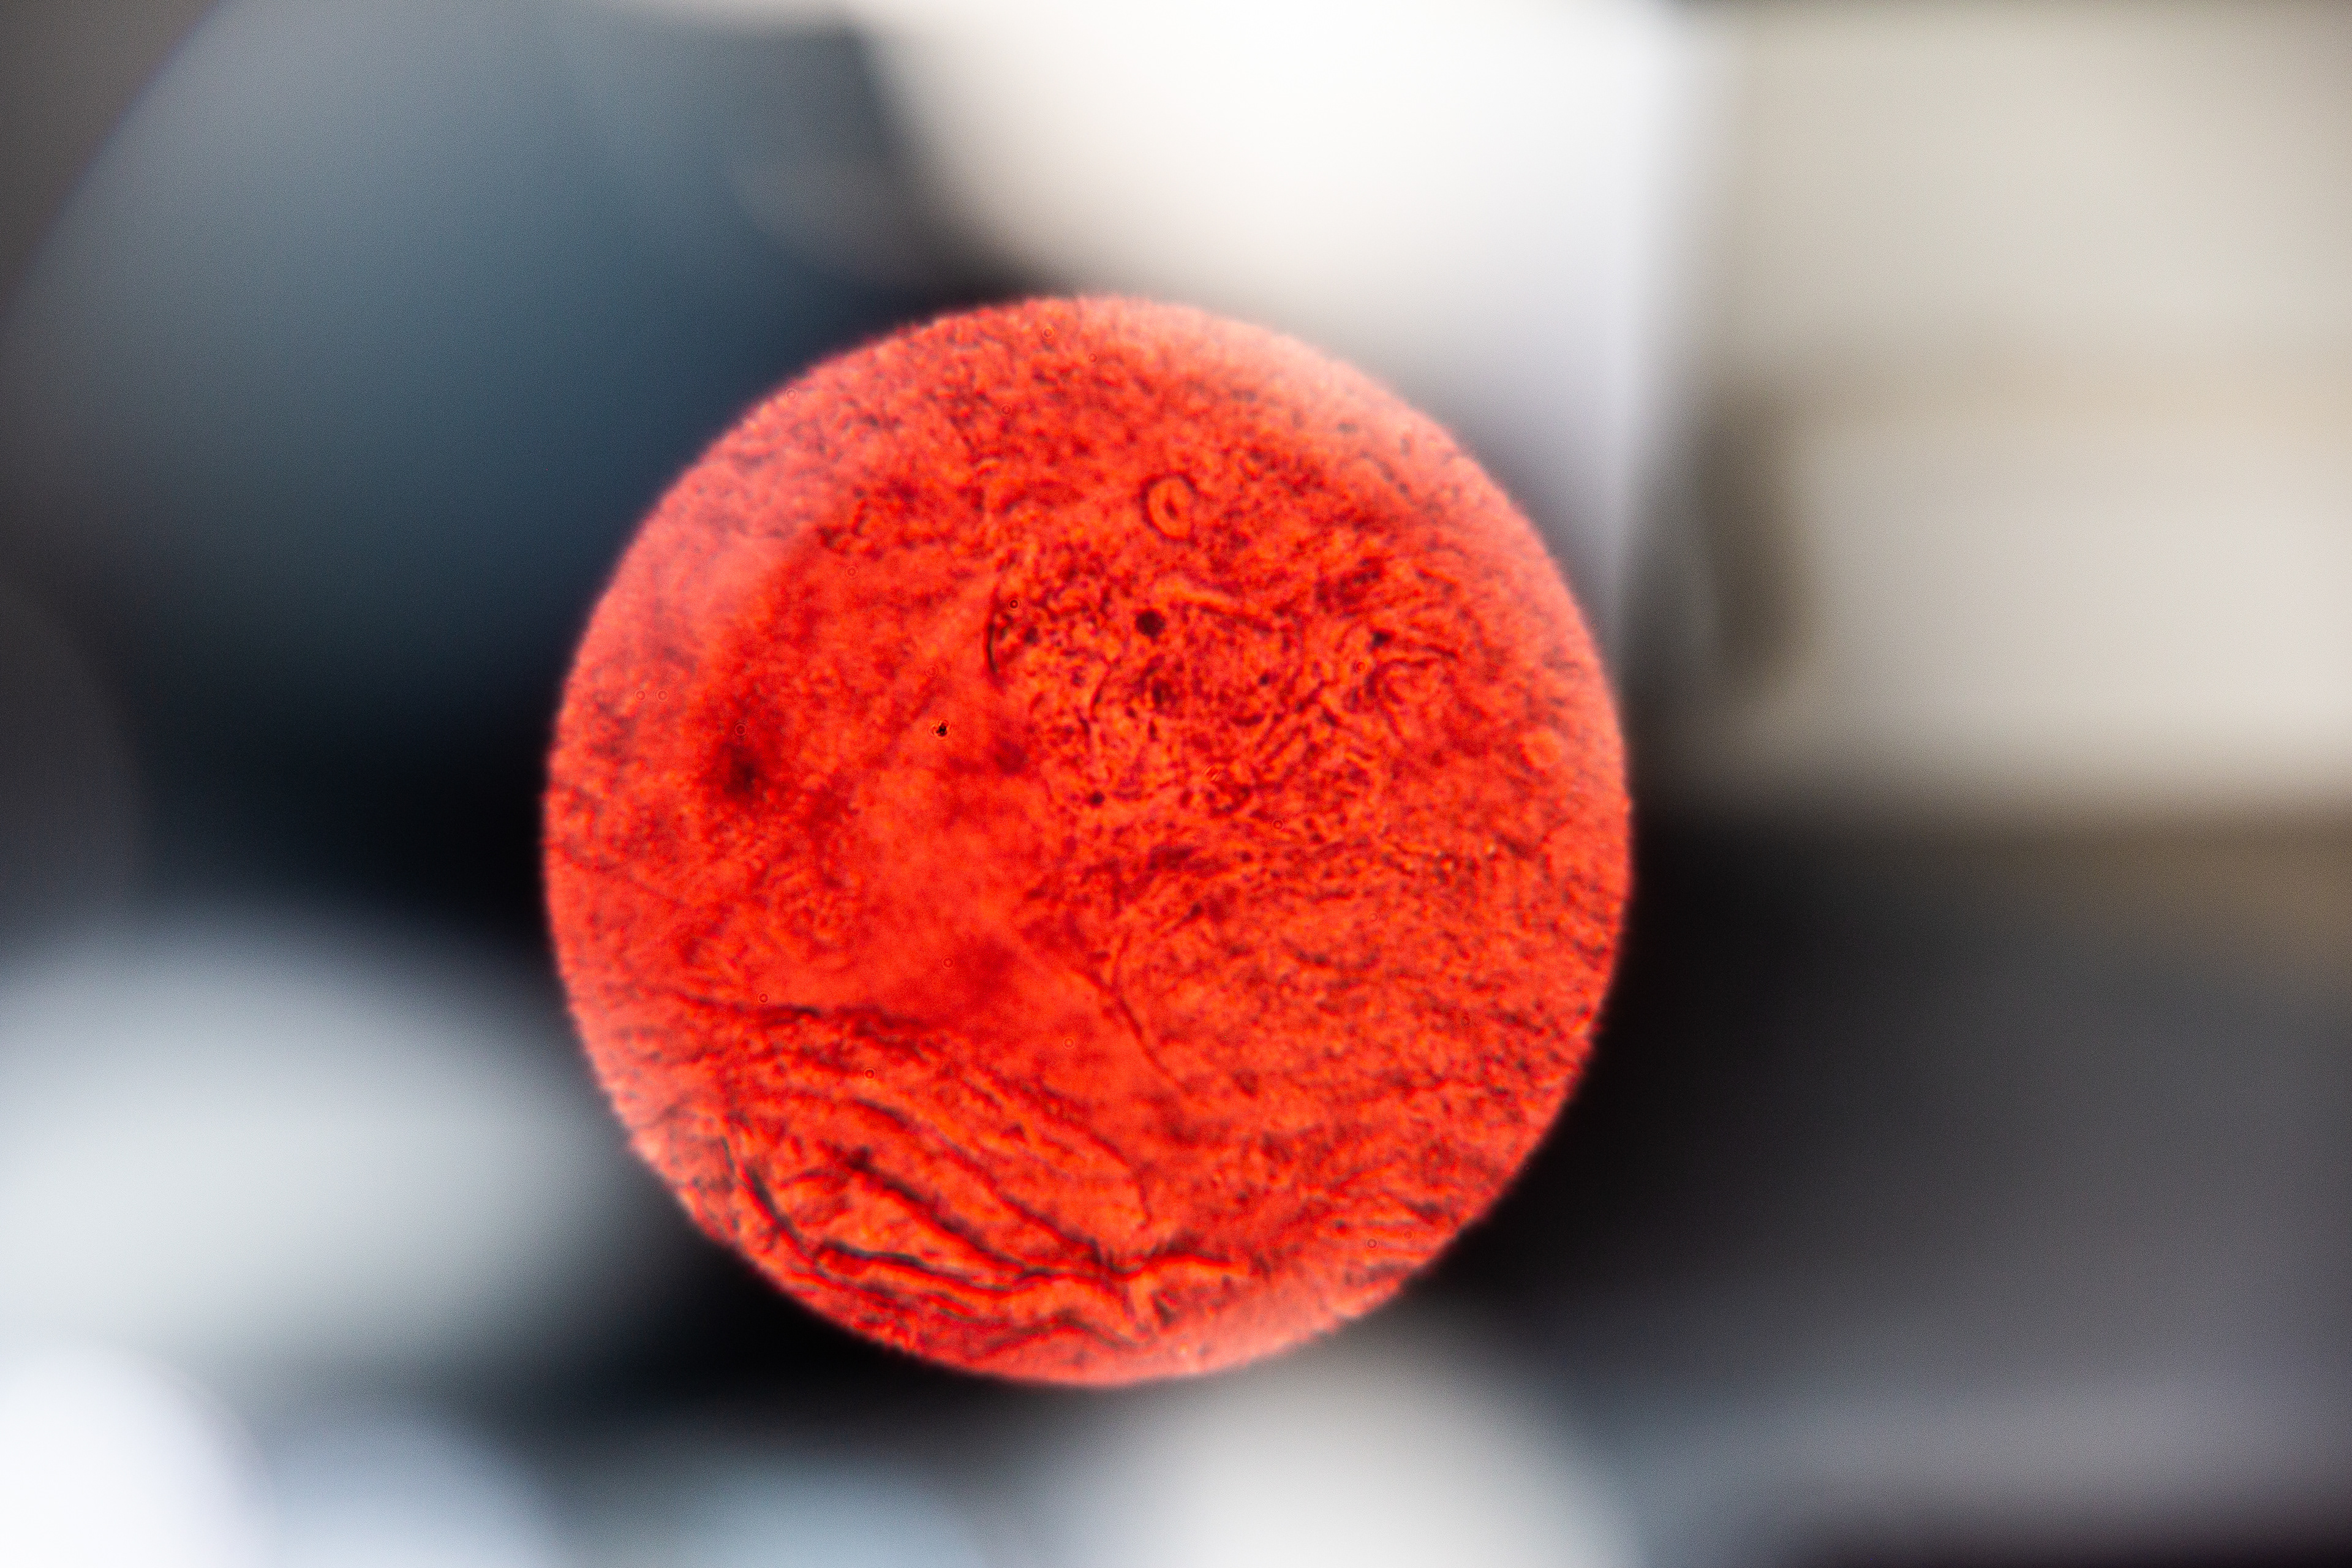

This got me curious. So, I collected and analyzed my own menstrual blood. First I took a look at my venous blood from my small finger and then compared it to my menstrual blood. The following pictures show my menstrual blood at different magnifications:

Menstrual Blood 100x